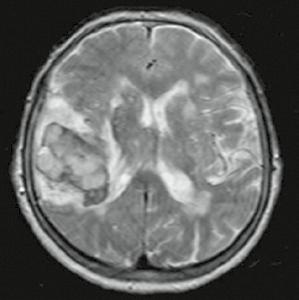

Kazuistika

Osmdesátiletá pacientka, z kardiologických důvodů dlouhodobě na warfarinu, hypertonička. Náhlé bezvědomí, pád z postele. Při přijetí somnolentní, jednoduchým výzvám vyhoví, hlavu a bulby stáčí doprava, levostrannými končetinami hůře pohybuje. Zemřela 5. den po mozkové příhodě.

Obr. A2.1–A2.4 Intracerebrální krvácení v akutním stadiu (1. den), oxyhemoglobin, ale již příměs deoxyhemoglobinu